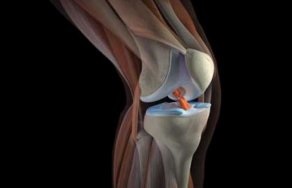

Meniscului este un strat de cartilaj în cavitatea articulației genunchiului, care servește ca amortizare și stabilizare. Astfel de straturi în genunchi două - interne și externe. ruptură de menisc apare de obicei din cauza.

Menisc - o formațiune flexibilă de țesut fibro cartilaginos în formă de semilună. În structura sa, meniscul este aproape de tendonul. În genunchi există două: externe și interne. Acestea sunt situate pe suprafata.

Se numește strat cartilaj meniscului articulației genunchiului, care se află între suprafețele de tibie și femur. Meniscului actioneaza ca un amortizor de șocuri și stabilizator. Dar o parte din presiune, în special în sport.